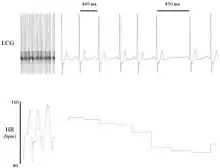

Heart rate variability (HRV) is the physiological phenomenon of variation in the time interval between heartbeats. It is measured by the variation in the beat-to-beat.

Other terms used include "cycle length variability", "R–R variability" (where R is a point corresponding to the peak of the QRS complex of the ECG wave; and RR is the interval between successive Rs), and "heart period variability".

Variation in the beat-to-beat interval is a physiological phenomenon. The SA node receives several different inputs and the instantaneous heart rate or RR interval and its variation are the results of these inputs.